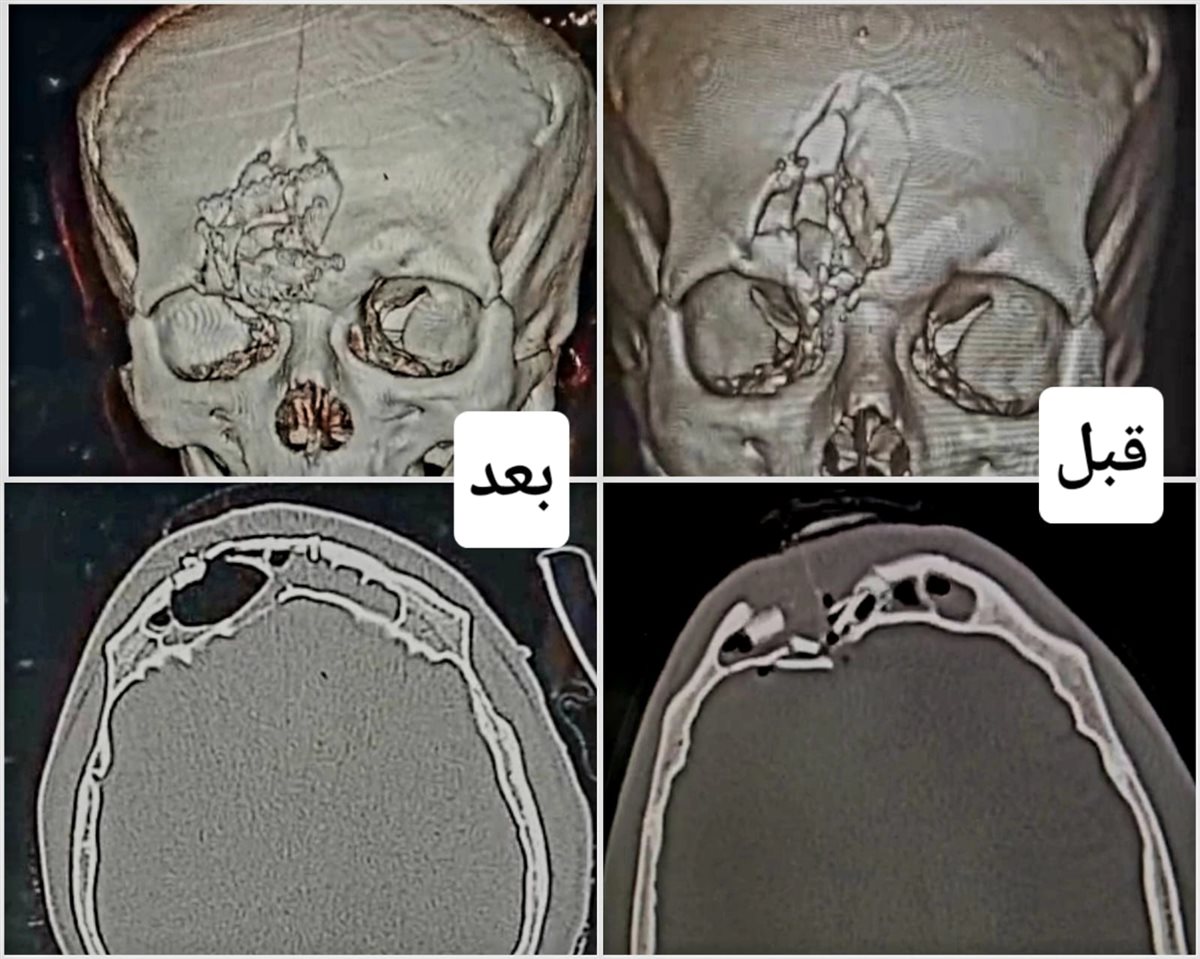

وأوضح وكيل الوزارة أن مستشفى تمى الامديد شهد إجراء جراحة معقدة لطفلة تبلغ من العمر 5 سنوات، وصلت إلى المستشفى إثر تعرضها لحادث طريق تسبب في كسر منخسف مضاعف بالجمجمة وضغط مباشر على العين اليسرى. وفور استقبال الحالة، تم تشكيل فريق طبي من جراحة المخ والأعصاب والتجميل والتخدير، حيث أُجريت عملية رد الكسر المضاعف بمحجر العين وتثبيته بشرائح ومسامير دقيقة، مما أسفر عن استعادة وظيفة العين بشكل كامل، وتتماثل الطفلة الآن للشفاء.

شارك في الجراحة الدكتور محمد سليم عودة، مدرس مساعد جراحة المخ والأعصاب بكلية الطب والدكتورمحمد فتحي، مدرس مساعد جراحة التجميل والدكتورة فاطمة محمد عبداللطيف، استشاري التخدير.